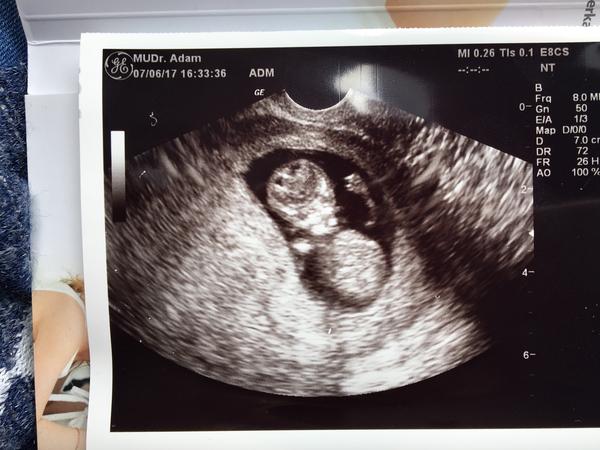

Baby,tak vsetko je v poriadku, vydledky z krvi su super 🙂 boooze,skoro som sa rozrevala ked som uvidela ako sa krasne hybalo...ruckami,nozickami..dokonca aj skackalo... chvilku si tvaricku suchalo ... nadherne to bolo ❤️❤️❤️❤️ TP tak ako som si vyratala: 30.12. a podla velkosti sme 10tt 6 dni,cize je asi o 3 dni vacsie ako podla MS... veeeelmi som stastna, dakujem ,ze ste na mna mysleli 😘😍

@milasik10 Gratulujem. Krásne je bábätko 🙂